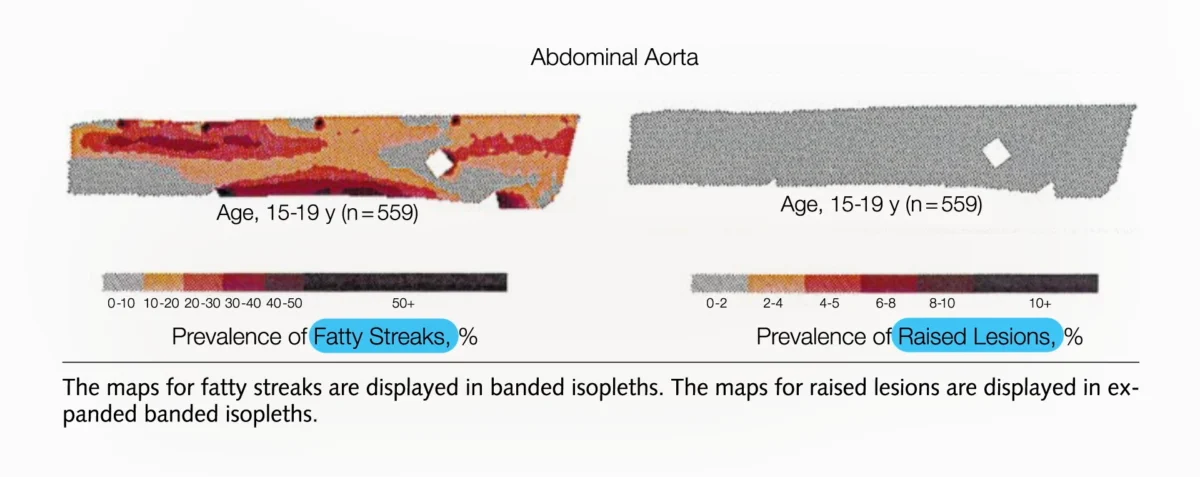

Beyond the Statin Debate: A Strategic Framework for Precision Lipid-Lowering Therapy and Cardiovascular Risk Management

The clinical landscape of cardiovascular preventative medicine is currently undergoing a paradigm shift, moving away from the binary question of whether to initiate statin therapy and toward a sophisticated, individualized…